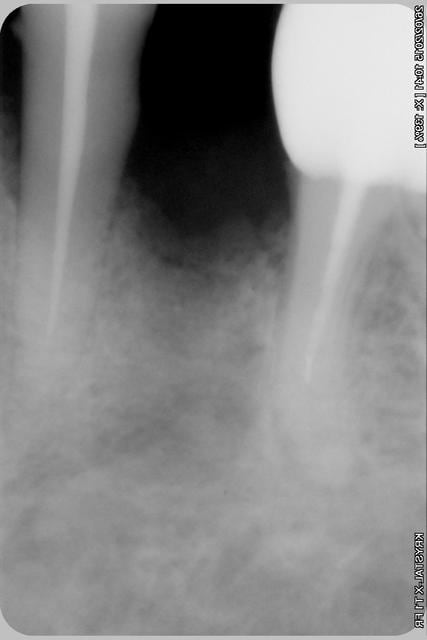

alors là pas du tout, le patient vient me voir pour des implants, donc je fais une étude du cas absence des molaires supérieures, couronnes mandibulaires très ancienne 45 racine cassée, 44 dévitalisée mais passablement déchaussée, donc avulsion de 45 et pose d'un implant avant de refaire les couronnes 46/47 et l'ensemble.

Échec implantaire, et oui ça arrive, même dans un cas paraissant simple.

je n'ai pas les radios ici...semaine prochaine.

Pour les septiques, toujours certain que c'est du sur-traitement?

Oui, un Px, le premier était un Reg.

l'os était tendre, ce qui explique le choix du Px